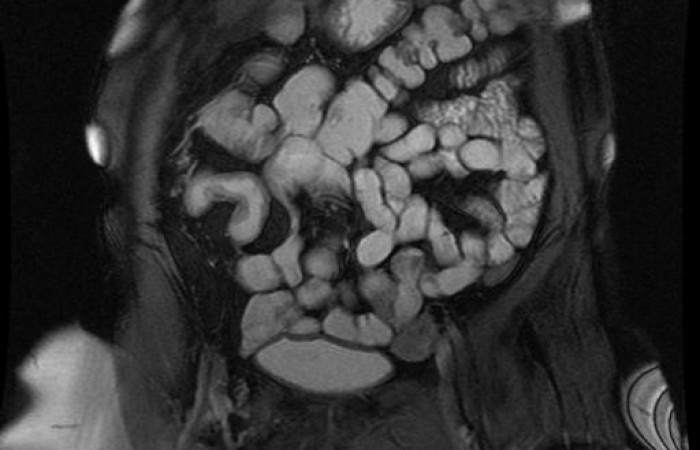

ˇ cholangiopankreatografia MR (MRCP) - badanie MR dróg żółciowych i trzustkowych bez podania środków kontrastowych